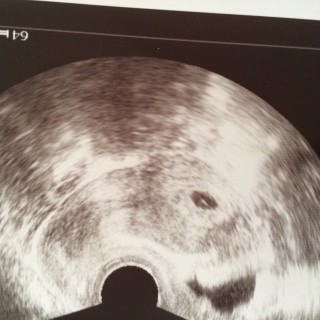

今日婦人科行ったら! まだ確認出来ないかもしれないと言われたたが、いざ内診すると確認出来たので良かった??(*´?`*)??? エコー写真の見方がまだ良く分かりませんヽ(;▽;)ノ

初めての妊娠でドキドキでしたが、正常妊娠でひと安心☆胎嚢は9.9ミリでした♪

先生から「妊娠してますね、正常妊娠ですよ」と言われて一安心でした。まだまだ小さいですけど、とっても愛おしい初めてのベビーたちゃんです。